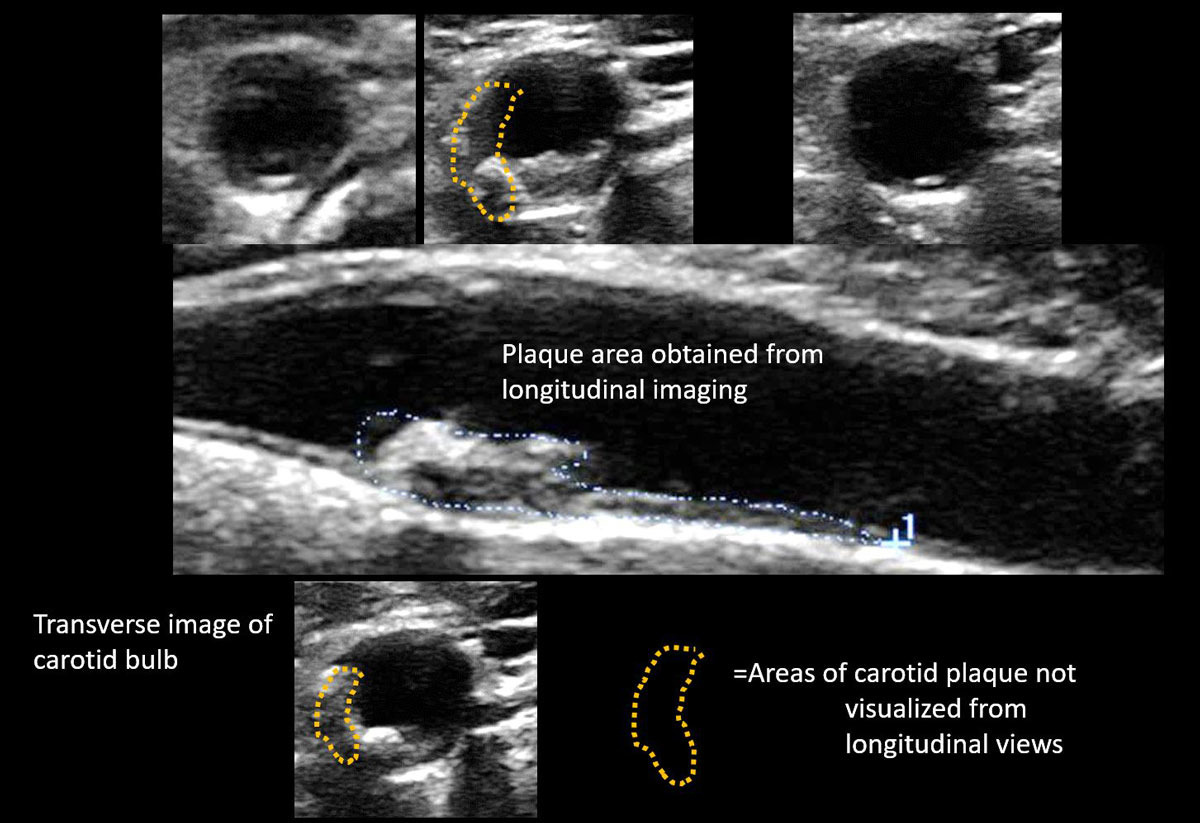

- 혈관 플라크(지방, 콜레스테롤 침착물)

플라크가 혈류에 영향을 줄 정도로 커지면 협착이 발생하고, 이 플라크 조각이 떨어져 나가 뇌혈관을 막으면 뇌경색이 발생할 수 있기에 조기 발견이 매우 중요합니다. 또한 IMT(혈관 내막-중막 두께) 수치가 정상보다 두꺼워진다면 심혈관 질환의 발병 가능성이 높은 것으로 평가됩니다. 즉, 경동맥 초음파 결과는 뇌뿐 아니라 심장 건강 상태를 간접적으로 나타내는 지표로도 활용됩니다. 특히 다음과 같은 상황에서 더 세밀한 해석과 대처가 필요합니다.

- 플라크 위치와 크기

- 협착률(혈관이 얼마나 좁아졌는지 퍼센트로 표시)

- IMT 수치(혈관 노화 및 동맥경화 지수)